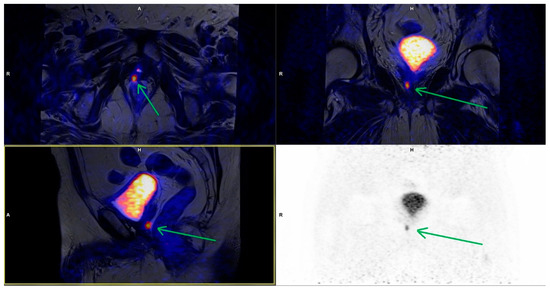

3.3. Bone Metastases

| Bones | 5 | 4.75 ± 1.82 | 5 × 4 up to 8 × 8 |